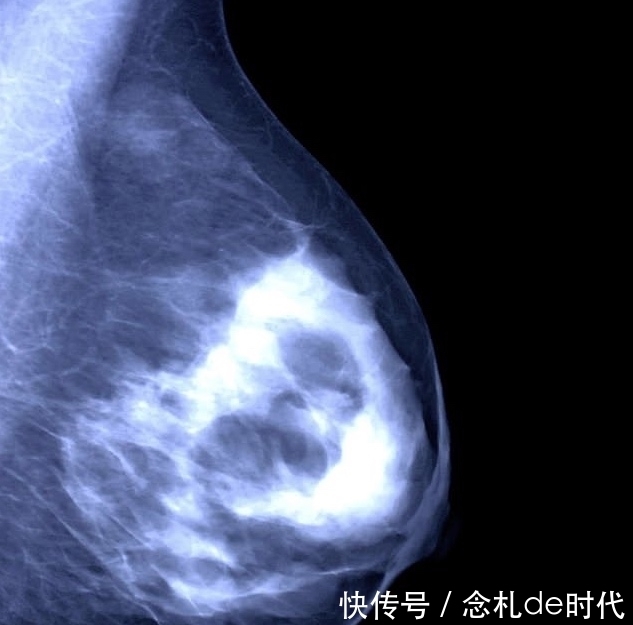

一种新的由激素+瑞博西尼(Ribociclib一种破坏癌细胞的靶向药物)的联合治疗,可以使成千上万名乳腺癌患者,延长生存期。

这种联合治疗方案可以使绝经前女性中的晚期乳腺癌患者的生存率有显著的提高。

将瑞博西尼(Ribociclib一种破坏癌细胞的靶向药物)添加到标准激素治疗中,与单独接受激素治疗的患者相比,死亡风险减少了近三分之一(29%)。

这项研究由洛杉矶加利福尼亚大学的Sara Hurvitz博士领导,研究跟踪了672名年龄在59岁以上未绝经的女性,这些女性患有晚期激素受体阳性,HER2阴性乳腺癌。

研究将患者分为两组,所有患者都接受激素治疗。区别一组采用有瑞博西尼(ribociclib)的联合治疗,另一组只是激素治疗。

42个月后,接受联合治疗的患者有70%仍然存活,而仅接受激素治疗生存的患者为46%。

研究还发现,接受ribociclib联合治疗患者的平均寿命为23.8个月。 而没有扩散,而仅接受激素治疗的患者则为13个月。

相关人士评价说: 这是最近10年来乳腺癌研究领域最大的突破!